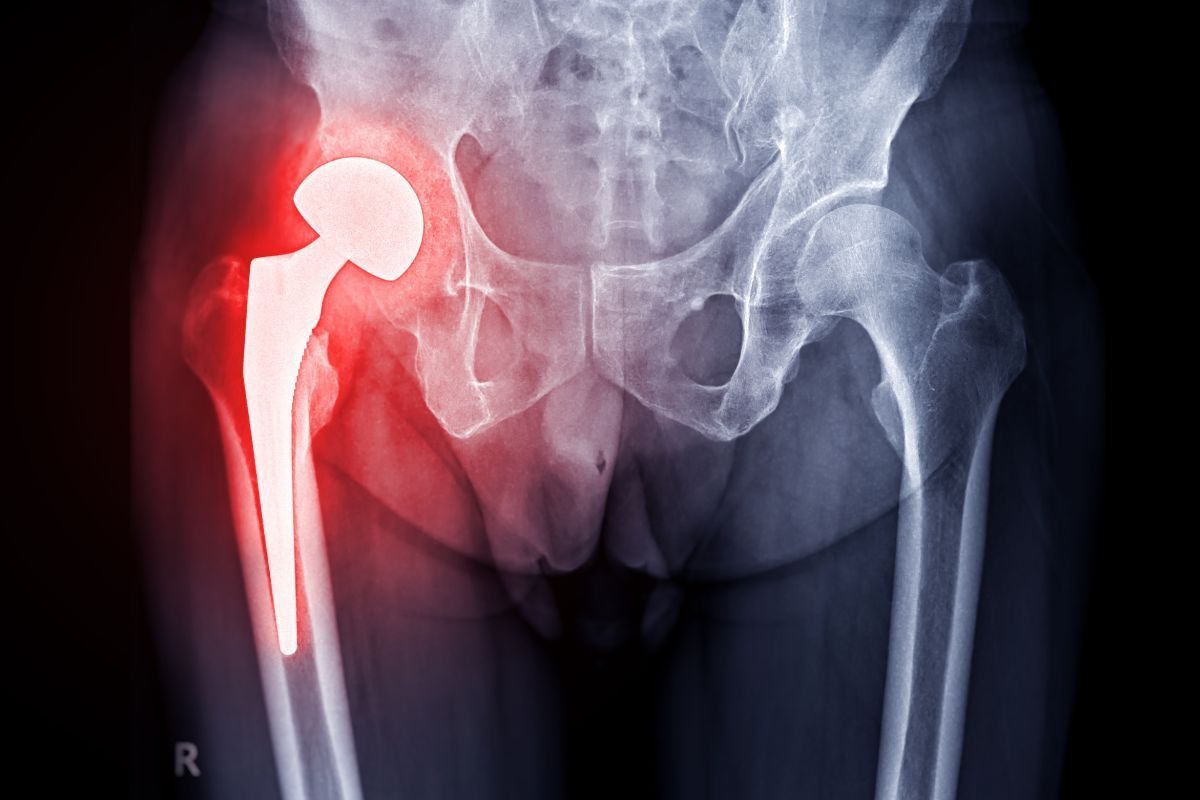

A prótese de quadril é um dispositivo médico projetado para substituir total ou parcialmente a articulação do quadril danificada, com o objetivo de aliviar a dor e restaurar a mobilidade.

Esse tipo de implante é indicado em casos de artrose avançada, osteonecrose, fraturas ou outras condições que comprometem a função articular.

Os principais componentes que formam uma prótese de quadril são:

- Componentes metálicos: geralmente feitos de ligas de titânio ou cromo-cobalto, materiais reconhecidos por sua resistência mecânica, durabilidade e alta compatibilidade com o tecido ósseo;

- Cabeças femorais: podem ser metálicas (liga de cobalto-cromo) ou cerâmicas, oferecendo baixo atrito e desgaste reduzido;

- Inserto (liner) acetabular: fabricado em polietileno de ultra-alto peso molecular (muitas vezes do tipo cross-linked, com maior resistência ao desgaste), cerâmica ou, mais raramente, metal.